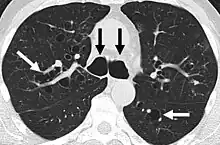

CT scan of the lungs showing findings diagnostic of bronchiectasis. White and black arrows point to dilated bronchi characteristic of the disease.

The goals of a diagnostic evaluation for bronchiectasis are radiographic confirmation of the diagnosis, identification of potential treatable causes, and functional assessment of the patient. A comprehensive evaluation consists of radiographic imaging, laboratory testing, and lung function testing.[63]

A chest x-ray is abnormal in most patients with bronchiectasis. Computed tomography is recommended to confirm the diagnosis and is also used to describe the distribution and grade the severity of the disease. Radiographic findings include airway dilation, bronchial wall thickening, and atelectasis.[3]